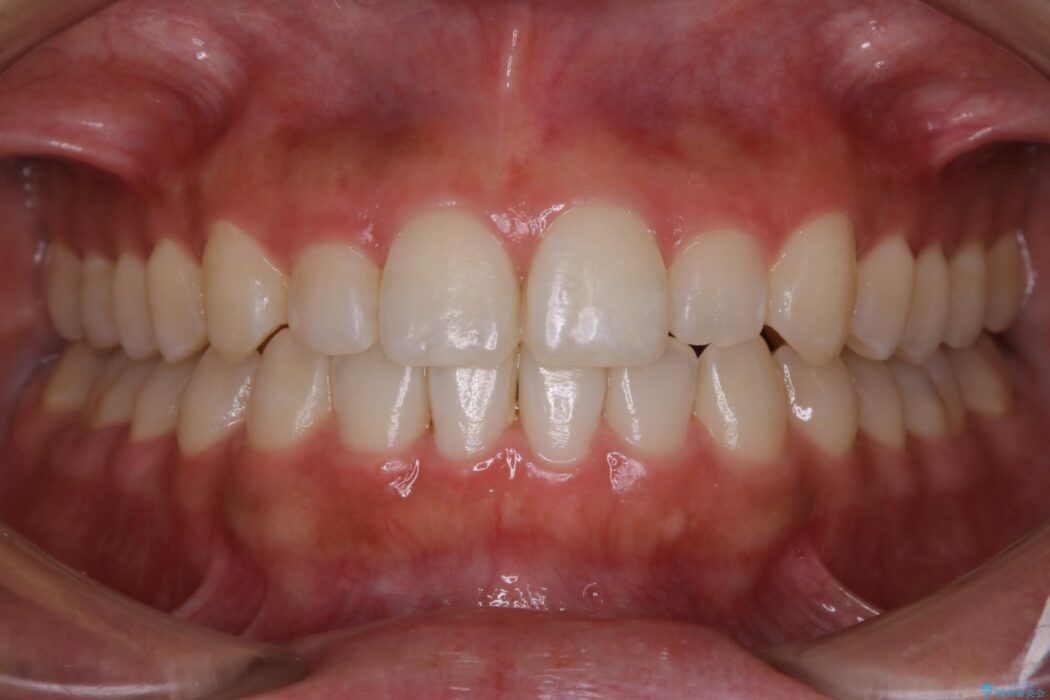

反対咬合の歯も整ったアーチに収まり、きれいに仕上がりました。

今回のケースでは前歯部の軽い凹凸のみであったため部分矯正の適応範囲に該当していました。

適応例は限られますが、部分矯正は全体矯正と比べると矯正期間が短く、費用も安く済みます。